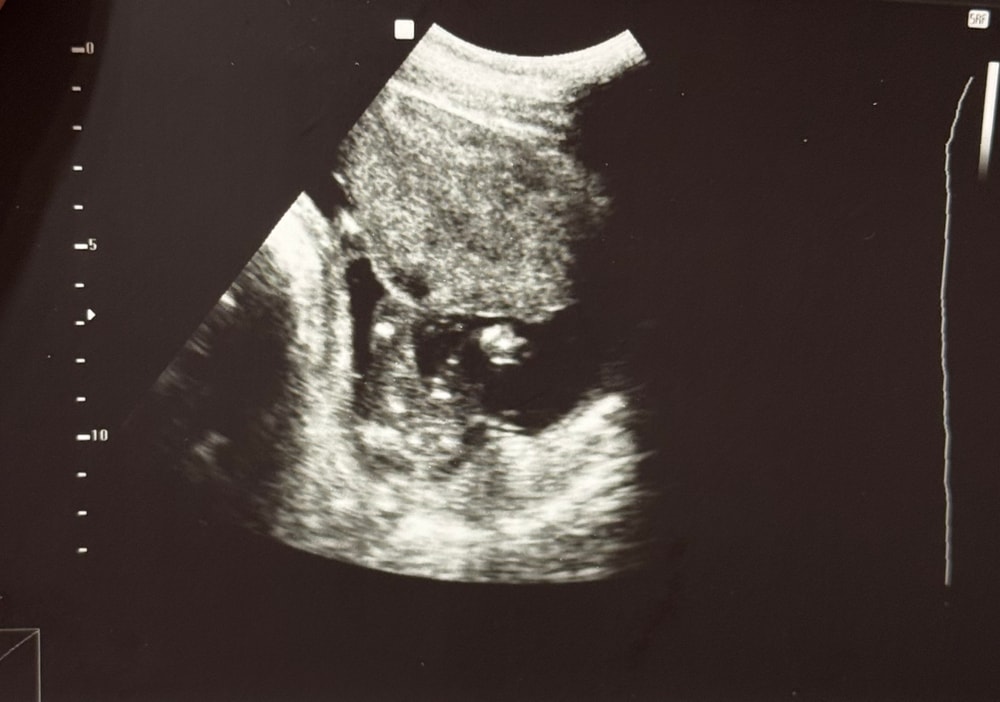

узи пол в 17+4 нед

Осмотр в беременность, вопросыДевочки, кто разбирается в УЗИ? Как думаете, кто у нас будет🙈 Фото в комментах

Если правильно поняла вид снизу, я бы подумала на девочку

Таро Расклады на зачатие , вчерашняя врач на таком сроке сказала, что не уверена, но насмотрела мальчика; А в 14+2 нед, была в этой же клинике и другая врач на таком сроке маленьком сказала - «100% мальчик будет», ну конечно я не поверила, тк срок маленький был очень, вот и пошла подтверждать вчера, а другая не уверена оказалась и дала вот это фото(

Да, вид снизу